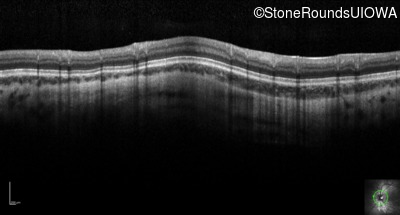

Optical Coherence Tomography - Right - 20/80 +2

Exemplar / OCT Stack

OCT Stack